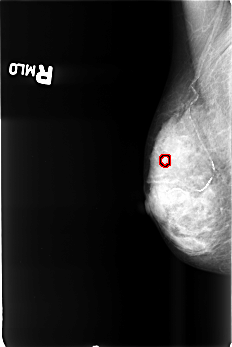

B_3437_1.RIGHT_MLO

RIGHT_MLO LINES 4504 PIXELS_PER_LINE 3008 BITS_PER_PIXEL 12 RESOLUTION 50 OVERLAY

FILE: B_3437_1.RIGHT_MLO.OVERLAY

TOTAL_ABNORMALITIES 1

ABNORMALITY 1

LESION_TYPE CALCIFICATION TYPE PLEOMORPHIC DISTRIBUTION CLUSTERED

ASSESSMENT 4

SUBTLETY 3

PATHOLOGY BENIGN

TOTAL_OUTLINES 1

BOUNDARY